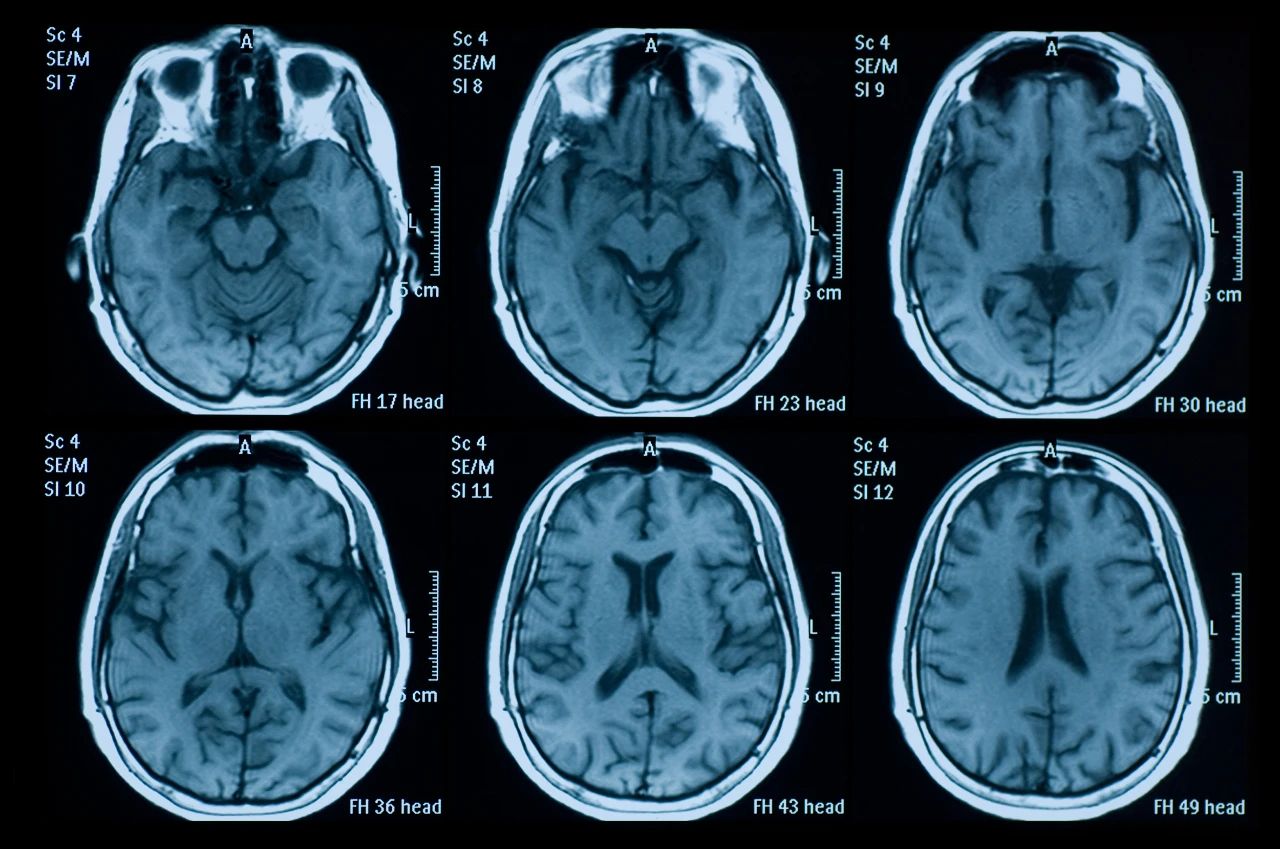

什么是創(chuàng)傷性腦損傷?

頭部受傷是頭部受到撞擊。它可能是輕微的,導致小腫塊或瘀傷,也可能更嚴重,導致腦損傷,如腦震蕩或腦出血。

即使您看不到頭部受傷也可能很嚴重。它們可能導致永久性殘疾或損傷,甚至死亡。更嚴重的頭部受傷總是需要去看醫(yī)生。